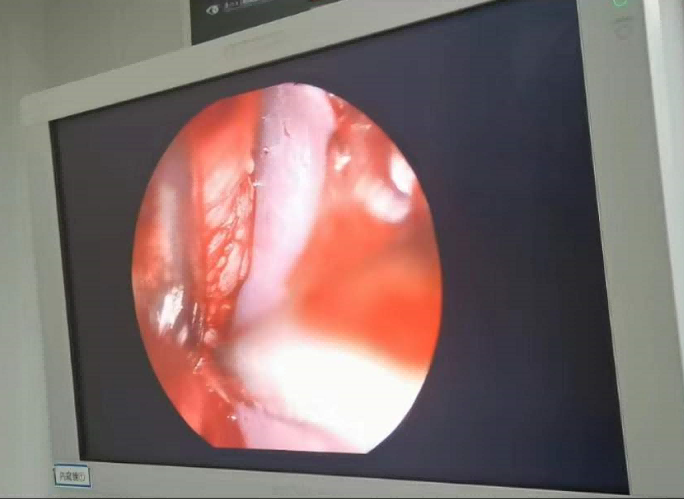

送到廈門眼科中心的時候,林老師受傷的左眼還在流血。眼整形科的鄧坤明副主任醫(yī)師緊急為他安排了“內(nèi)鏡下眶骨折修補+鈦網(wǎng)鈦釘植入術(shù)”。

圖為:內(nèi)鏡下眼眶骨折修補術(shù)

手術(shù)過程中林老師還出現(xiàn)了驚險的眼球后大出血,還好鄧坤明于緊急之中穩(wěn)住了病情,并順利完成了手術(shù)。術(shù)后第二天,林老師的術(shù)后反應(yīng)就很輕,恢復(fù)良好,他一邊感謝著鄧坤明的“救命之恩”,一邊自嘲著自己示范了個“反面教材”。